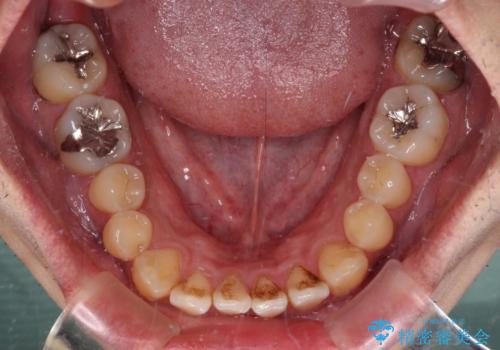

内側に引っ込んだ歯を治したい インビザラインの矯正治療

- 前歯のデコボコとクロスバイトを治したいとのことで来院された患者様です。

上下顎ともに歯列全体の側方拡大とIPR(歯と歯の間を削る)によってデコボコとクロスバイトが解消するように設計し、インビザラインにより治療を行うこととしました。

反対咬合特有の治療途中の前歯の干渉が長く続き、治療中に食事をとりにくく、ご迷惑をおかけしました。

前歯の咬み合わせの調整などを行い、安定した咬み合わせに仕上げることができました。